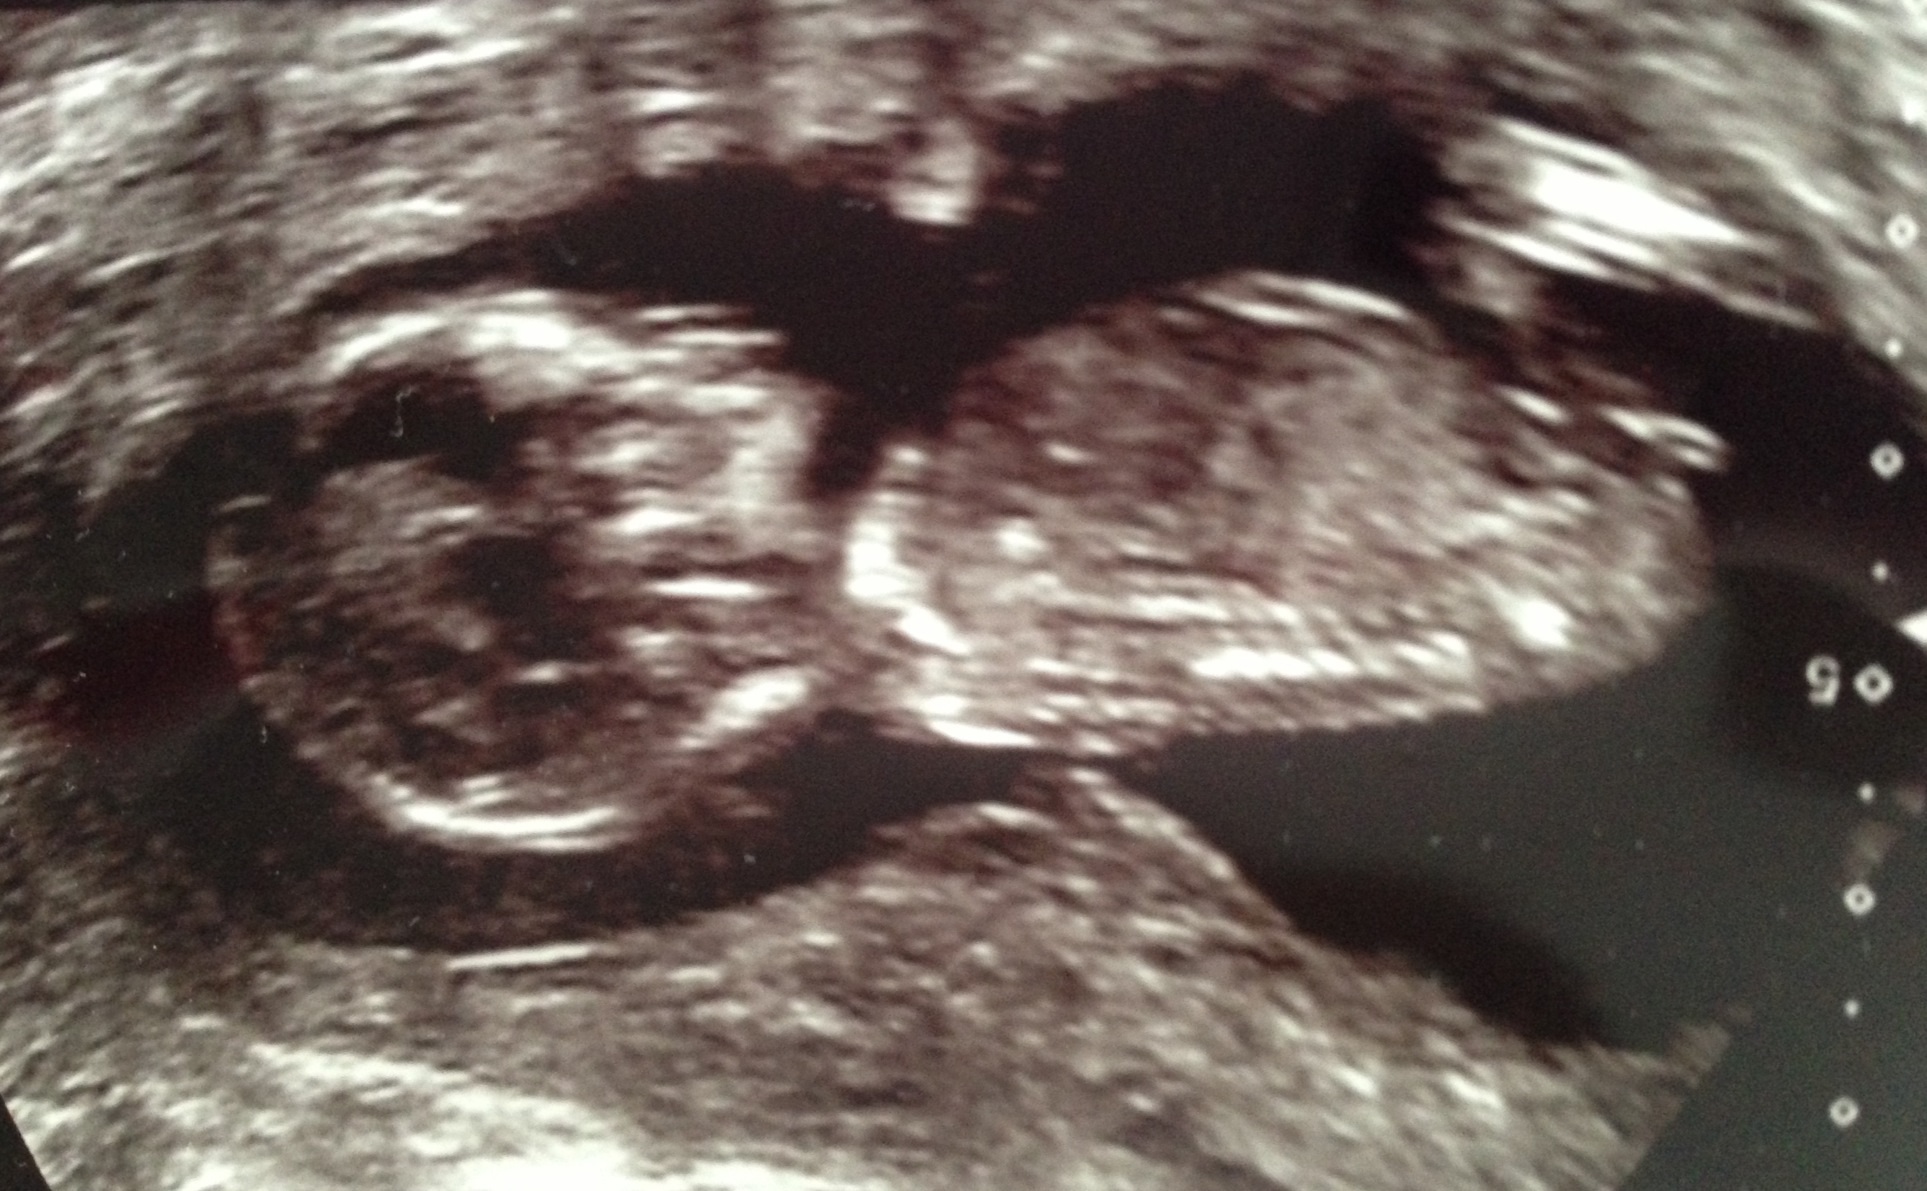

Attachment 19438

Her she is :awe::HH: xx